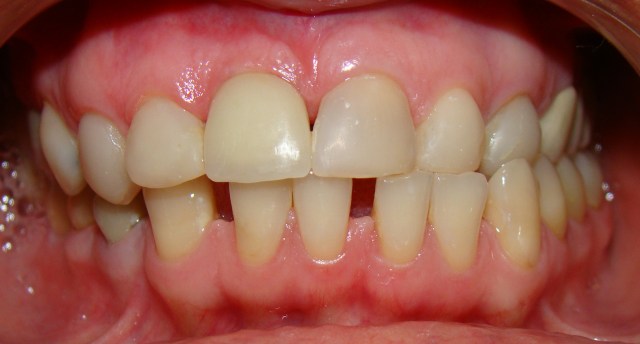

» Caso 1 - Reabilitação Oral Complexa

Paciente apresentava algumas ausências dentárias, principalmente posteriores e perd...